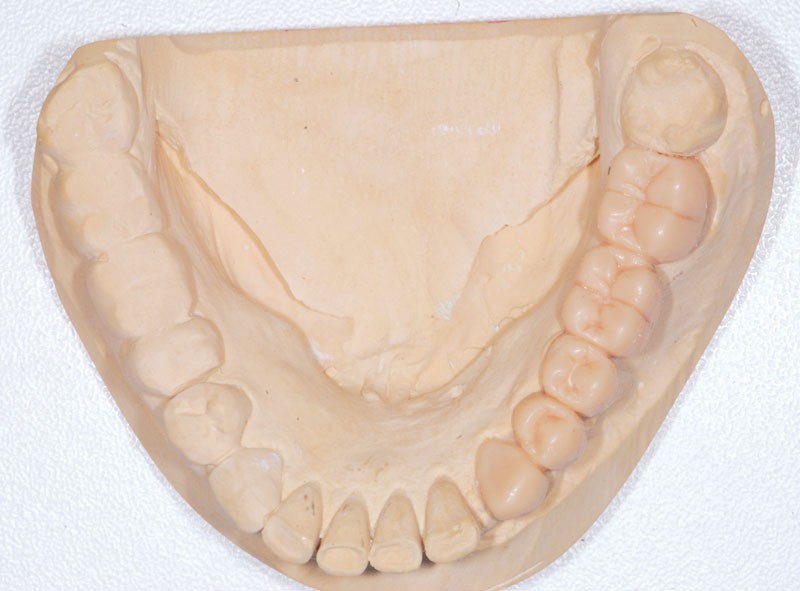

Après dépose du bridge mandibulaire et reprise du traitement endodontique, un bridge transitoire est réalisé à partir du wax-up. Une empreinte de celui-ci est faite avec Imprint™ 4 Preliminary Penta™ (3M ESPE).

L’automoulage est garni avec une résine composite (Protemp™ 4, 3M ESPE), avant ajustage et finition (roues spirales Sof-Lex™, 3M ESPE), pose du bridge transitoire.